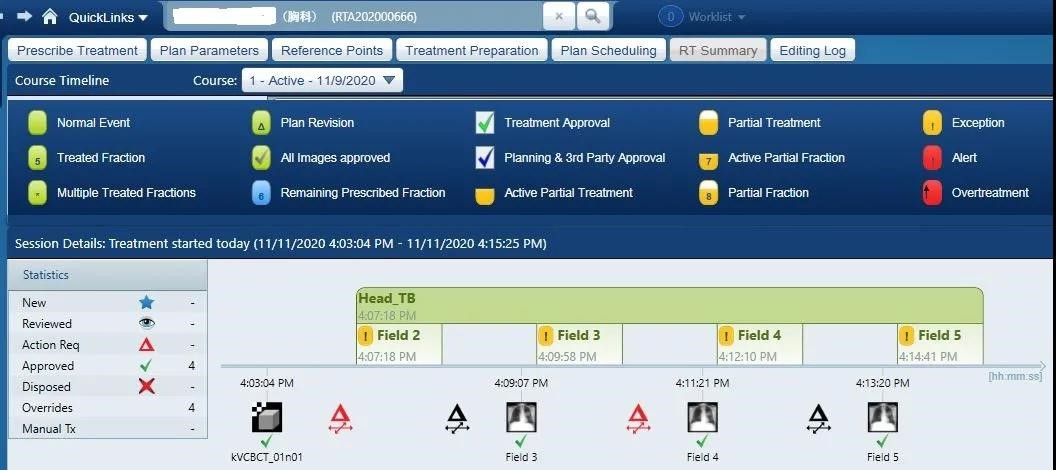

2020年10月28日,首例HyperArc治疗开展,全程共10分钟,其中出束开始到治疗结束不到5分钟。因为治疗的高度自动化,技师无需进入治疗室重新对患者进行摆位或者手动移床,治疗时间远远低于常规非共面治疗。